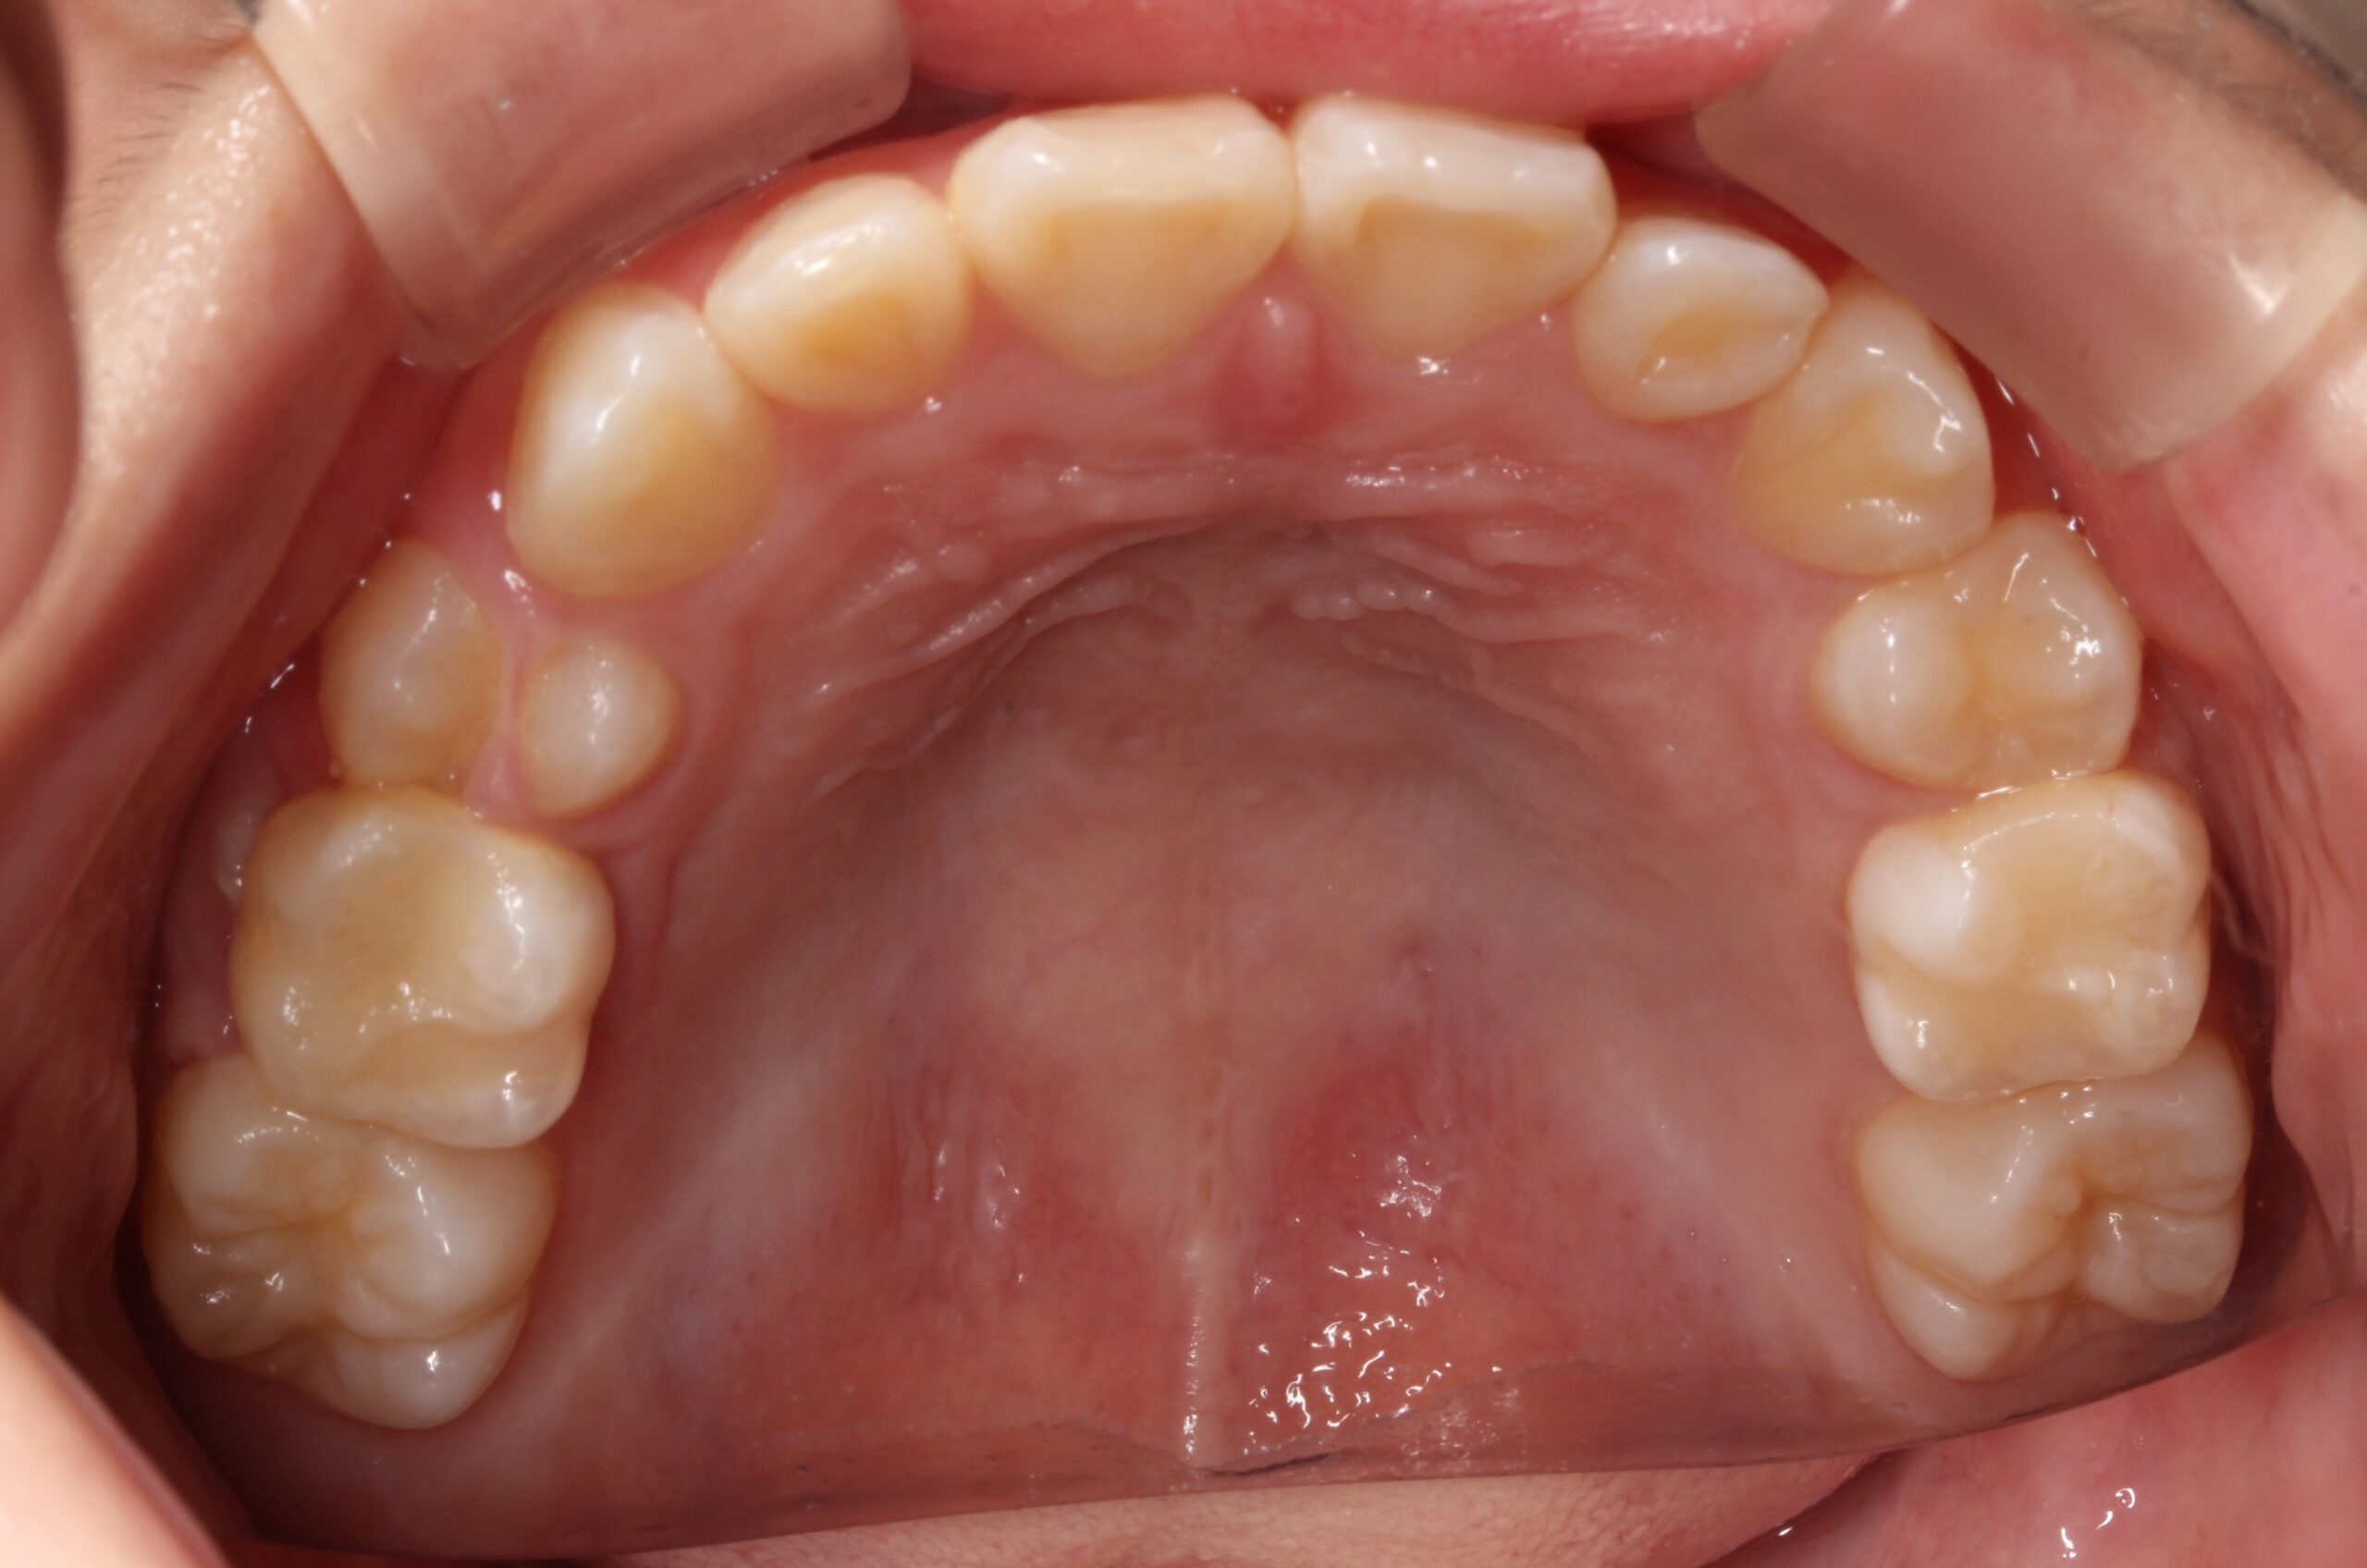

矯正術前:下顎

矯正術後:下顎